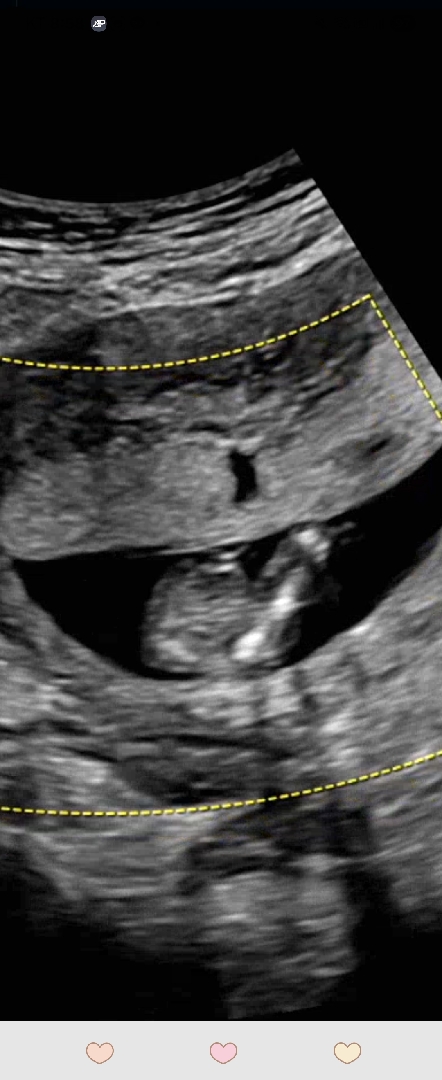

14주차 다리사이

다리사이가 14주에 매끈하면 16주도 매끈하죠? 딸원하는데요....